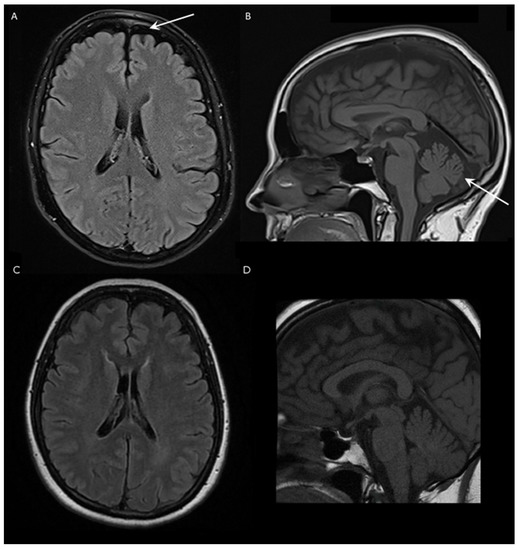

The first complaints of the patient presented in this report were episodic gait disturbance and dizziness at the age of 62. These problems first occurred only in the mornings, the duration of the episodes were 1.5 h; within 2 years, these episodes became longer and sometimes occurred during the afternoon as well. She had divergent strabism from childhood, as well as lumbar discopathy and hypothyroidism, due to Hashimoto thyroiditis. No similar gait difficulty was reported in her family. The neurological examination revealed strabism divergent on the left, horizontal gaze-evoked nystagmus, mild bilateral hypoacusis, slightly excavated feet, moderate spasticity in the ankles, mild paresis in both peroneal muscles, slightly slower fast alternating movements in the feet, mild gait ataxia, dysmetria and intention tremor in the upper limbs, slight ataxia in the lower extremities and discrete vibration hypesthesia in the feet. Dysarthria, ocular dysmetria, hyperreflexia, Babinski sign and extrapyramidal symptoms were not observed. The Scale for the Assessment and Rating of Ataxia (SARA) of the patient was 5 out of 40 in 2021, and the score did not progress during the following year. Nerve conduction studies did not detect polyneuropathy. Brain MRI examination showed mild cerebellar atrophy with vermian predominance and shrinkage of the frontal lobe with similar severity (Figure 1). Additionally, a small T2 hyperintense, T1 hypointense lesion was detected in the corpus callosum; however, its size decreased in the last 2 years. The spinal cord MRI did not demonstrate myelopathy. The video head impulse test revealed decreased vestibulo-ocular reflex on the left side and positional nystagmus on the right side. The cervical vestibular evoked myogenic potential test was absent on the right side and normal on the left side. Brainstem auditory evoked potential was normal. Detailed laboratory investigation did not detect obvious secondary etiology in the background of the ataxia. Serum levels of creatine kinase, albumin, B12, folic acid and alpha fetoprotein were all normal as well. The ANA, anti-TPO and antichromatin antibodies were positive in the last 2 years.

The clinical phenotype of the subject is characterized by slowly progressive episodic mild cerebellar symptoms, slight spasticity in the ankles and vibration hypesthesia in her feet. Similar neurological abnormalities were described in a Chinese family, although with more severe signs, which is supported by the difference in the SARA scores as well (Supplementary Table S1) [3]. Except mild spasticity in the ankles, no other upper motor neuron symptoms or movement disorders were noticed in the patient described in this case, although these neurological alterations were frequently observed in other cases [5,6,7,8,9,10]. Brain MRI examination showed mild cerebellar and frontal lobe atrophy, but no brainstem shrinkage, bilateral olivary degeneration or any other specific structural alterations were found.

Figure 1. Brain magnetic resonance imaging (MRI) of a Hungarian SCA40 patient and an age-matched healthy subject. (A) Fluid-attenuated inversion recovery (FLAIR) axial and (B) T1-weighted sagittal scans of the patient. The arrows indicate the frontal lobe and cerebellar atrophy, respectively. (C) FLAIR axial and (D) T1-weighted sagittal images of a healthy age-matched female.